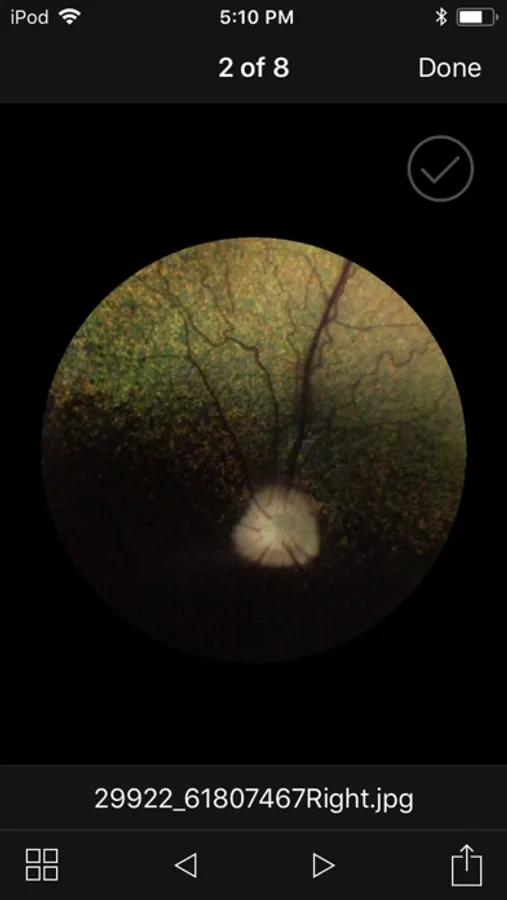

Award winning veterinary retinal imaging app for use with the Optibrand ClearView2 retinal imaging attachment. Using an iPhone or iPod Touch and a Optibrand ClearView2 retinal imaging attachment gives veterinarians and veterinary ophthalmologists an affordable and easy to use method for obtaining retinal images for purposes of disease diagnosis, general visualization, owner education, and record retention. ClearView2 uses patented auto capture technology that eliminates the need for operators to manually capture images.

ClearView2 Screenshots

Screenshot 1Screenshot 2Screenshot 3